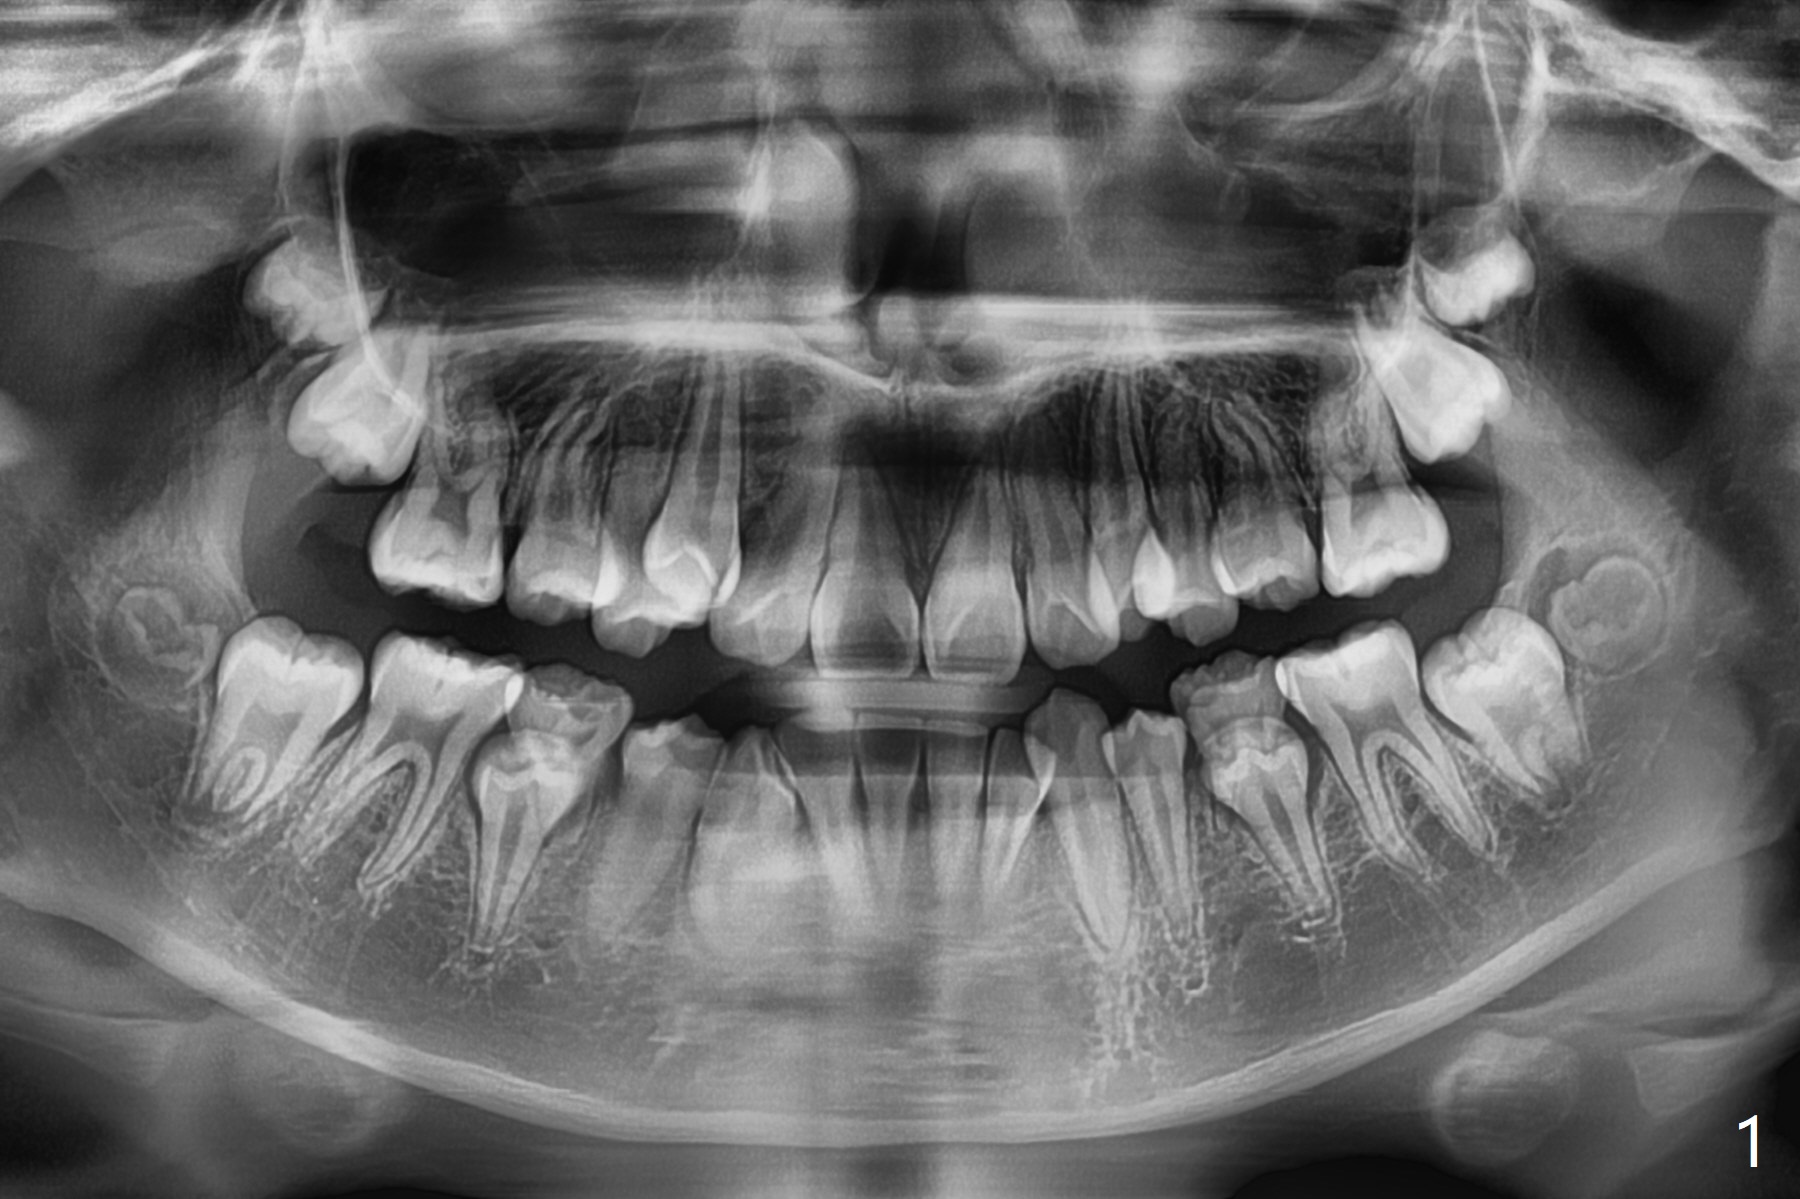

A 10-year-8-month-old woman presents to clinic with severe crowding (especially at the canines, Fig.1), but her facial profile is within normal limit (Fig.2,3) in spite of the fact that cephalometric tracing shows bimaxillary protrusion (Fig.4). Will 4 bicuspids' extraction affect her profile? Her mom requests immediate treatment, although the patient's oral hygiene is questionable.

Dear Dr. Shaughnessy: Can you review the following case? Is it too early to initiate the case as the mom wants? Should we extraction L Es first and 4 bi next? Or together now? After 1st bi ext, distalization of only 3s should not affect the facial profile? Thanks.

If the crowding is as severe as it appears, I would have no problem extracting the 1st premolars and Es prn. U will not change the profile much at all if any if severe crowding because you will have only small space to close. Do remember from the start that I will need Class I molars so do what it takes to end up there! If you fall short, you finish with xs overjet.Return to